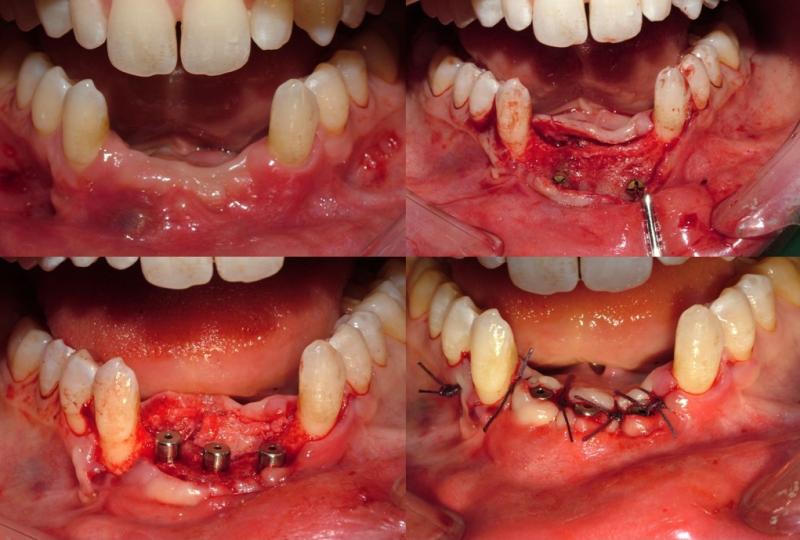

Dento-alveolar surgery (impacted teeth like wisdom teeth and canines, difficult tooth extractions, extractions on medically compromised patients, apicoectomy, bone grafting/bone harvesting or pre-prosthetic surgery) (See Images Below)

Surgery to insert osseo-integrated dental implants and Maxillofacial implants for attaching craniofacial prostheses (See Images Below)